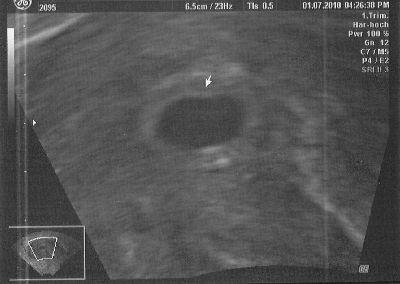

Das ist am 1. Juli entstanden - bei 5+2 - noch (*hoff*) eine leere Fruchthöhle, aber an der richtigen Stelle. Meine Gebärmutter ist nach hinten "gekippt", sodass mein FA sagte, dass alles okay ist und man das Baby noch nicht sehen muss - die Fruchthöhle war zumindest zeitgerecht entwickelt...

Nachtrag: Achja - bei unserer Tochter hat man zu dem Zeitpunkt auch nur eine leere Fruchthöhle gesehen - und das beunruhigt mich gar nicht. Mittwoch sollte man das Krümelchen dann aber schon sehen können...